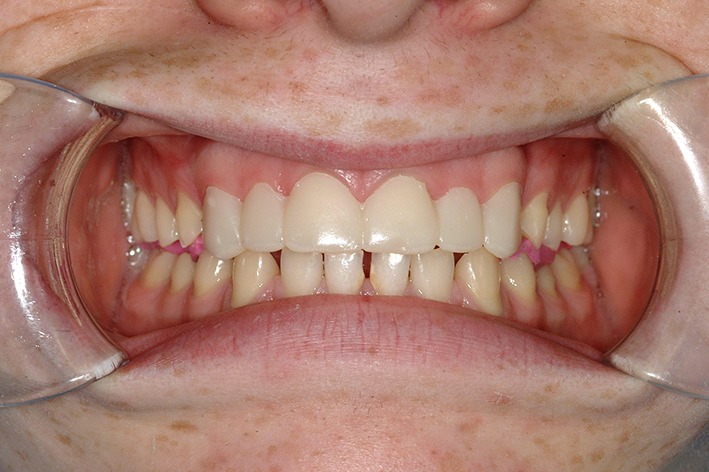

A 17 year old patient, also referred to a teaching hospital, was complaining of the appearance of his anterior teeth due to erosion from a history of excessive intake of carbonated drinks (Coca Cola). On presentation, he had completely stopped his intake of carbonated drinks over the previous 12 months. Prior to that, however, he consumed at least one litre of carbonated drinks per day. He presented with severe wear of his upper teeth (Fig. 10) together with wear affecting the occlusal surfaces of his posterior teeth. He had excellent oral hygiene and in addition to brushing with a fluoride toothpaste twice daily, he was also using a fluoride mouth rinse.

Fig. 10.

Pre-operative buccal view